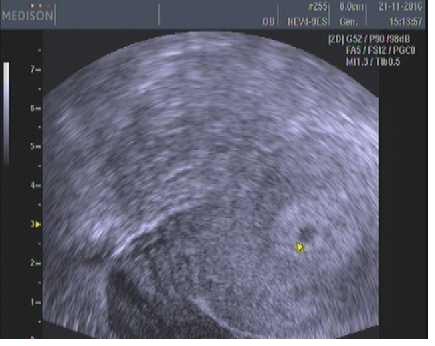

Jinak já jsem po 1. IVF, už 7. den od ET jsem měla //, minulý týden na UTZ potvrzeny dvě bublinky, dneska jsem 5tt+4 a už se do ničeho nevejdu - mám dojem, že s dvojčátkama bude všechno mnohem intenzivnější a rychlejší 😀